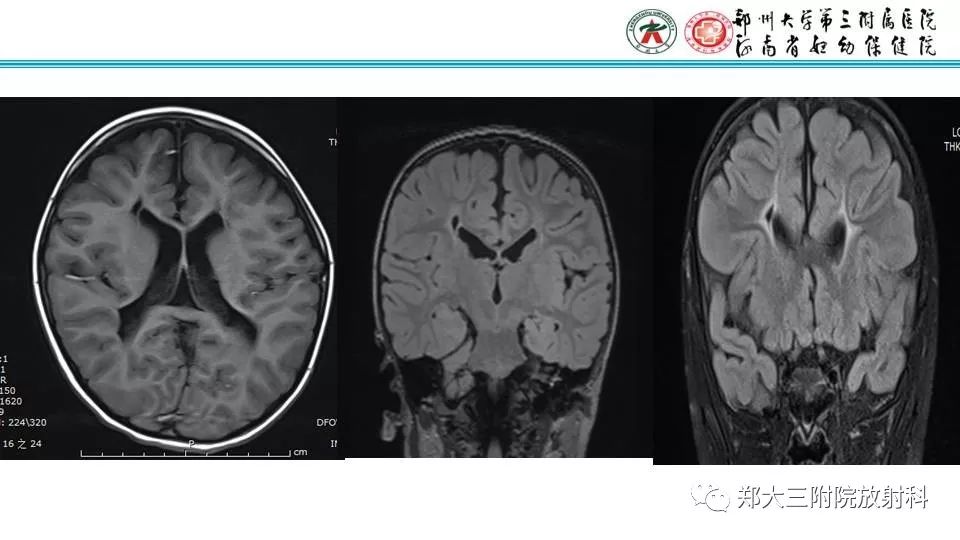

【PPT】室周假性囊肿-4